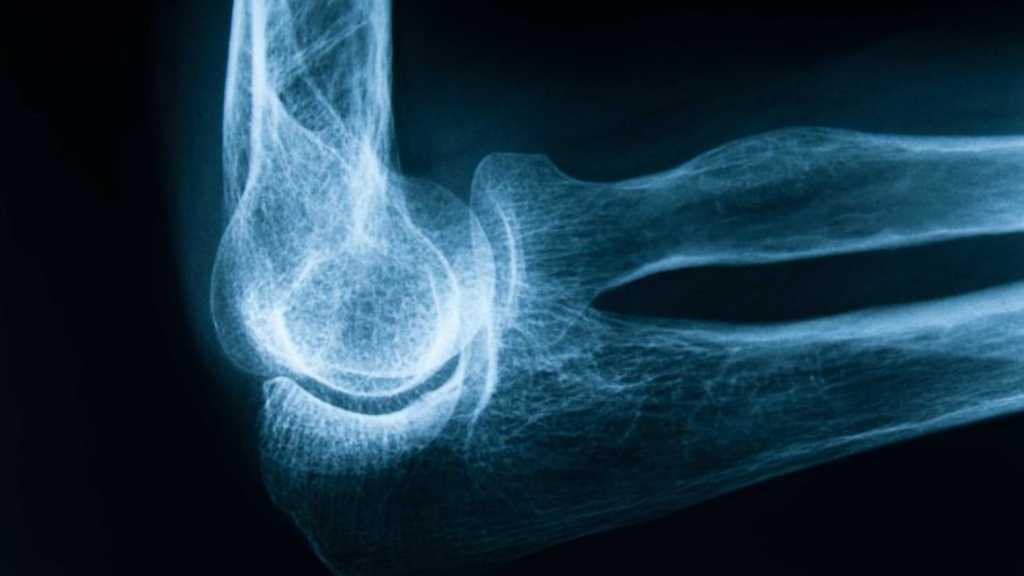

5. Anda memiliki kepadatan tulang yang rendah

Ilustrasi (iStock)

Kadang-kadang disebut osteopenia, kepadatan tulang yang rendah berarti kepadatan tulang Anda —jumlah kalsium dan mineral— lebih rendah dari rata-rata. Namun, ini tidak berarti bahwa Anda akan menderita osteoporosis. Itulah yang dikatakan Dr. Vokes bisa sangat sulit tentang osteoporosis. Tandanya benar-benar tak terkira.

"Ini tidak memberi Anda gejala kecuali bahwa tulang lebih rapuh dan mungkin patah," katanya. Jika Anda memang memiliki kepadatan tulang yang rendah, Dr. Vokes menyarankan untuk melakukan tes kepadatan tulang secara teratur untuk mengetahui osteoporosis sebelum terjadi patah tulang.